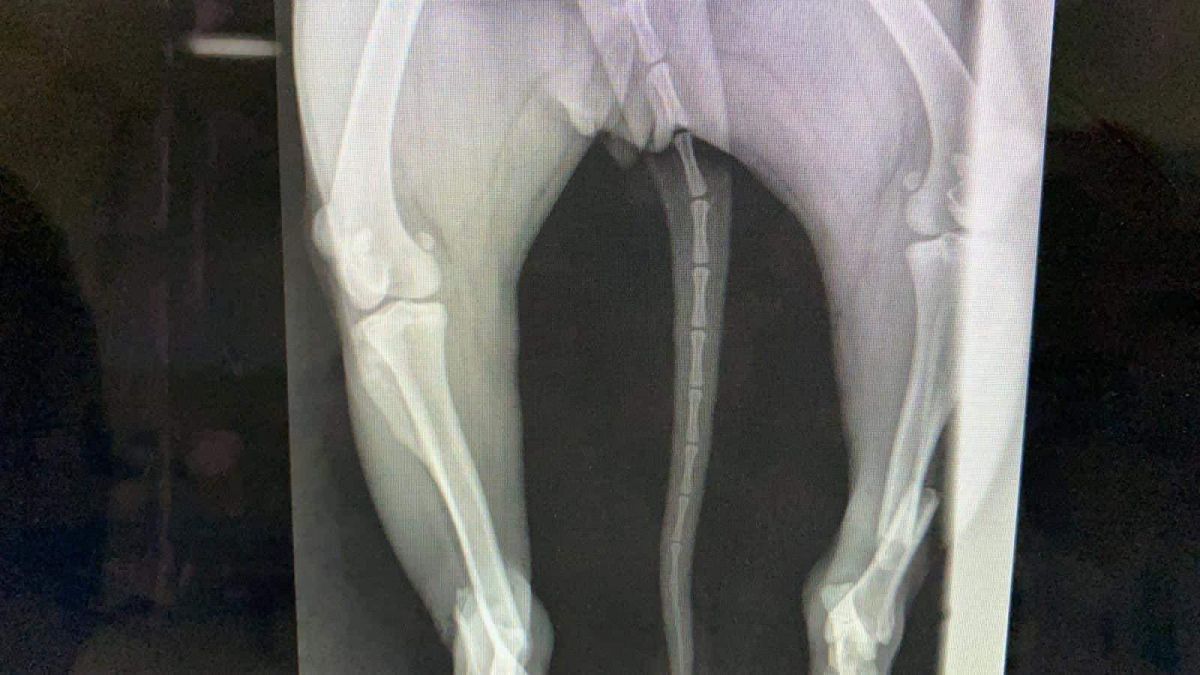

Prinsă în laț și bătută cu atâta cruzime încât i-au rupt picioarele, cățelușa a fost adusă de niște oameni miloși în cabinetul medicilor veterinari.

În urma investigațiilor și radiografiilor s-a confirmat că ambele membre posterioare prezentau fracturi duble, unul din membre cu fractura semideschisă, însă încă prezentau sensibilitate”,

Operația s-a realizat de urgență, totul a decurs bine, dar există în continuare risc de infecție, astfel că va mai rămâne internată câteva zile în clinică, recuperarea fiind una de durata.